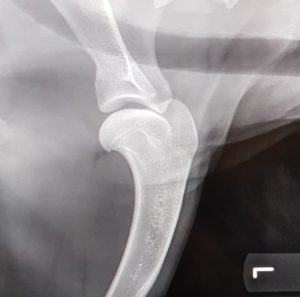

Endnu 2 hunde er blevet bedømt af DKK og fundet HD, AD og OCD frie, vi er så glade og stolte!